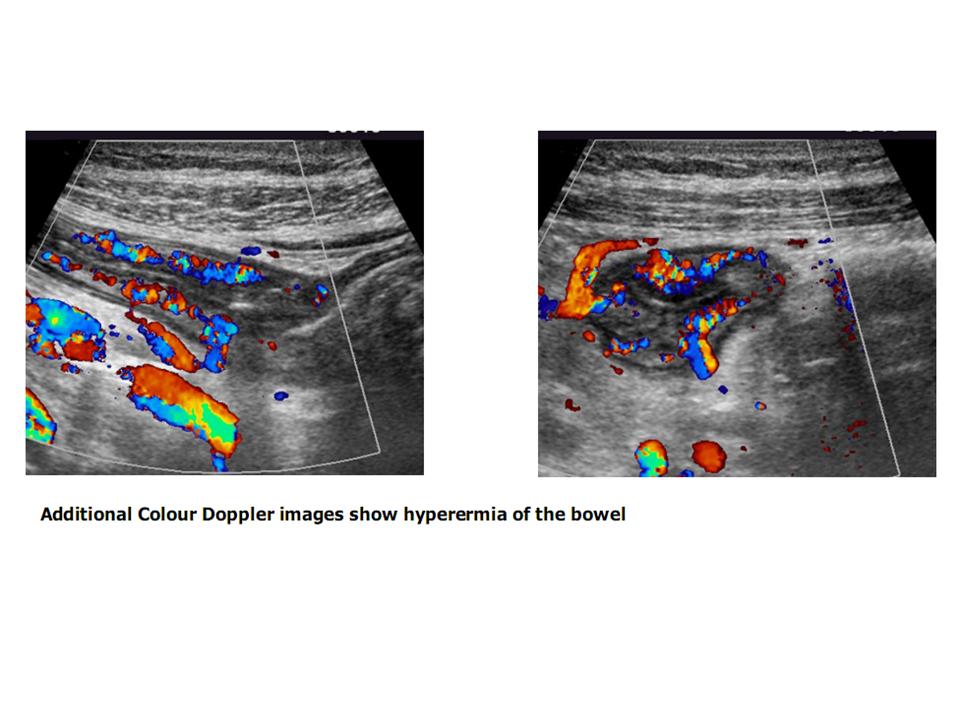

after the patient has fasted. Use of contrast material has been found to

increase accuracy, and Doppler evaluation of bowel wall vascularity may help to

determine the presence of disease activity or quiescence.